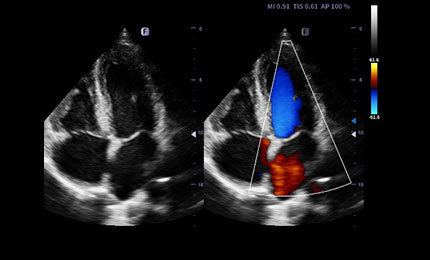

Zastosowania: Brzuch,

Położnictwo, Ginekologia

Zastosowania: Położnictwo,

Ginekologia, Urologia